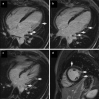

The Society for Cardiovascular Magnetic Resonance (SCMR) is an international society focused on the research, education, and clinical application of cardiovascular magnetic resonance (CMR). The SCMR web site ( https://www.scmr.org ) hosts a case series designed to present case reports demonstrating the unique attributes of CMR in the diagnosis or management of cardiovascular disease. Each clinical presentation is followed by a brief discussion of the disease and unique role of CMR in disease diagnosis or management guidance. By nature, some of these are somewhat esoteric, but all are instructive. In this publication, we provide a digital archive of the 2019 Case of the Week series as a means of further enhancing the education of those interested in CMR and as a means of more readily identifying these cases using a PubMed or similar search engine.